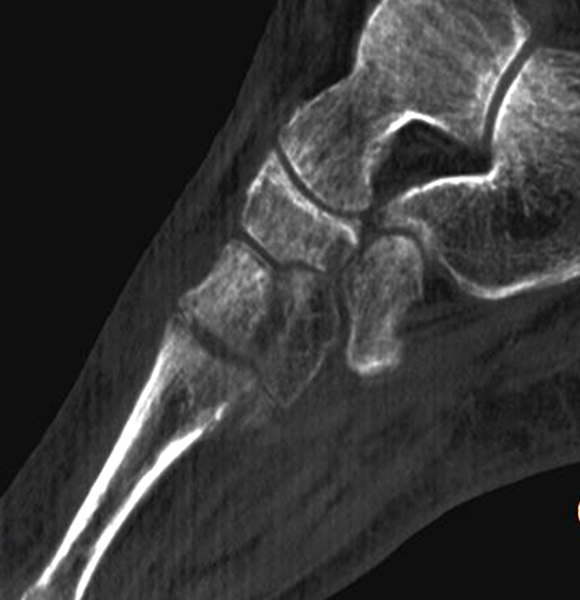

Die Abbildungen 4.2.a bis d zeigen den typischen Aspekt einer talacalcanearen Coalitio. Es besteht nur eine linksseitige, symptomatische Coalitio talocalcaneare (4.2.a und c); das 35 Tage zuvor angefertigte MRT zeigt keine auffälligen Signalveränderungen (4.2.b und d).